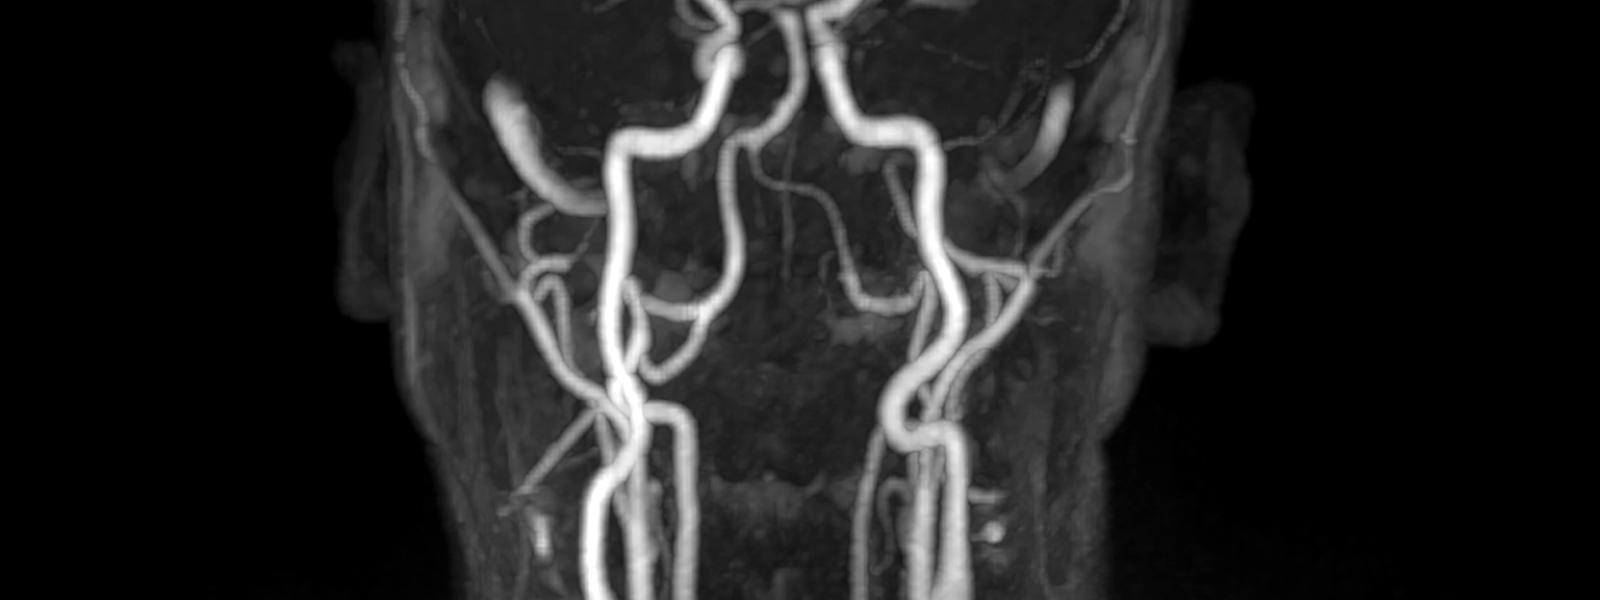

MU Health Care, which performs 700 to 800 neuro interventional procedures each year, began the transition in 2019. The doctors eased into the new technique by using the radial approach only for diagnostic angiograms — a relatively simple procedure that isn't time-sensitive. Unlike the femoral approach, which offers a "straight shot" to the brain, the radial approach requires maneuvering the catheters and wires through a reverse N-shaped path up the arm, down to the aortic arch and up again into the carotid, subclavian or vertebral arteries. They developed a new workflow and found slightly different catheters and wires more suited to the relevant twists and turns.